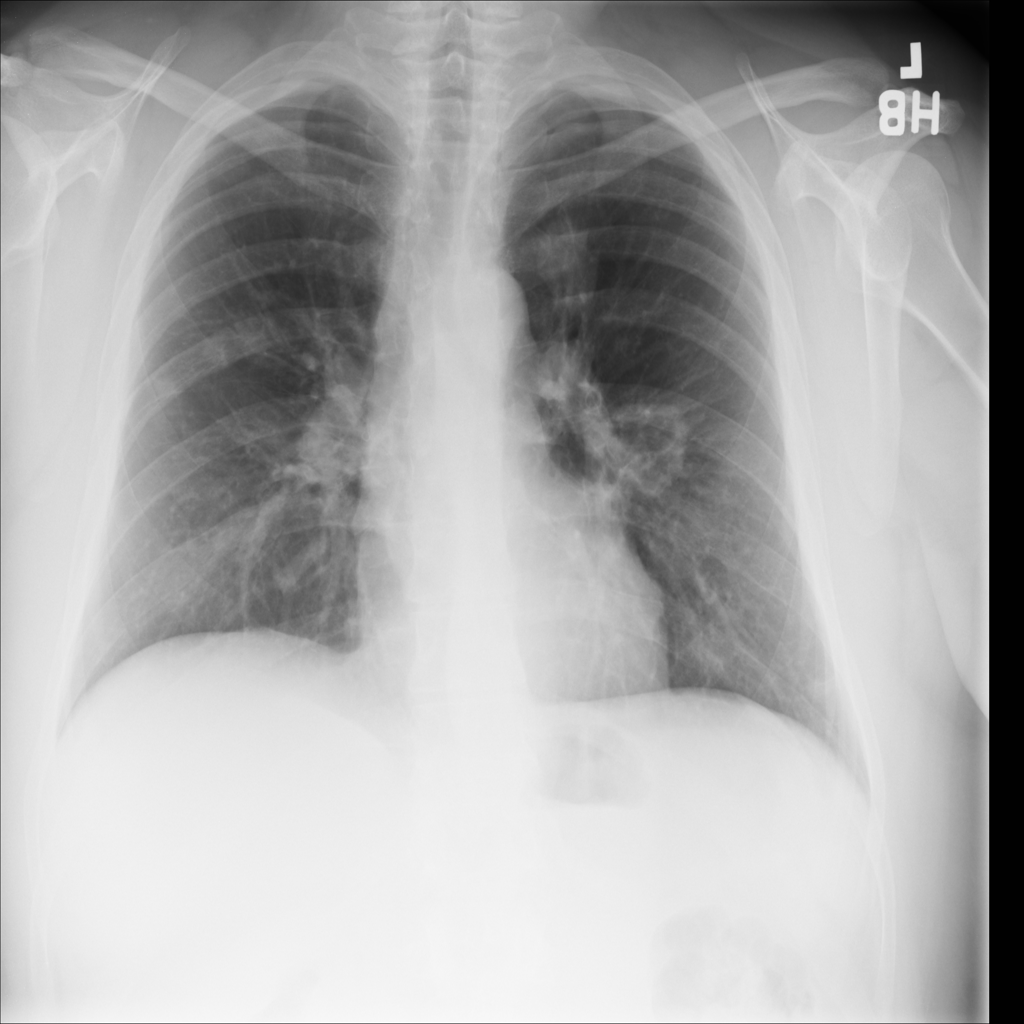

PAT-C0E5 · IMG-001Mass

PAT-C0E5 · IMG-001

PA